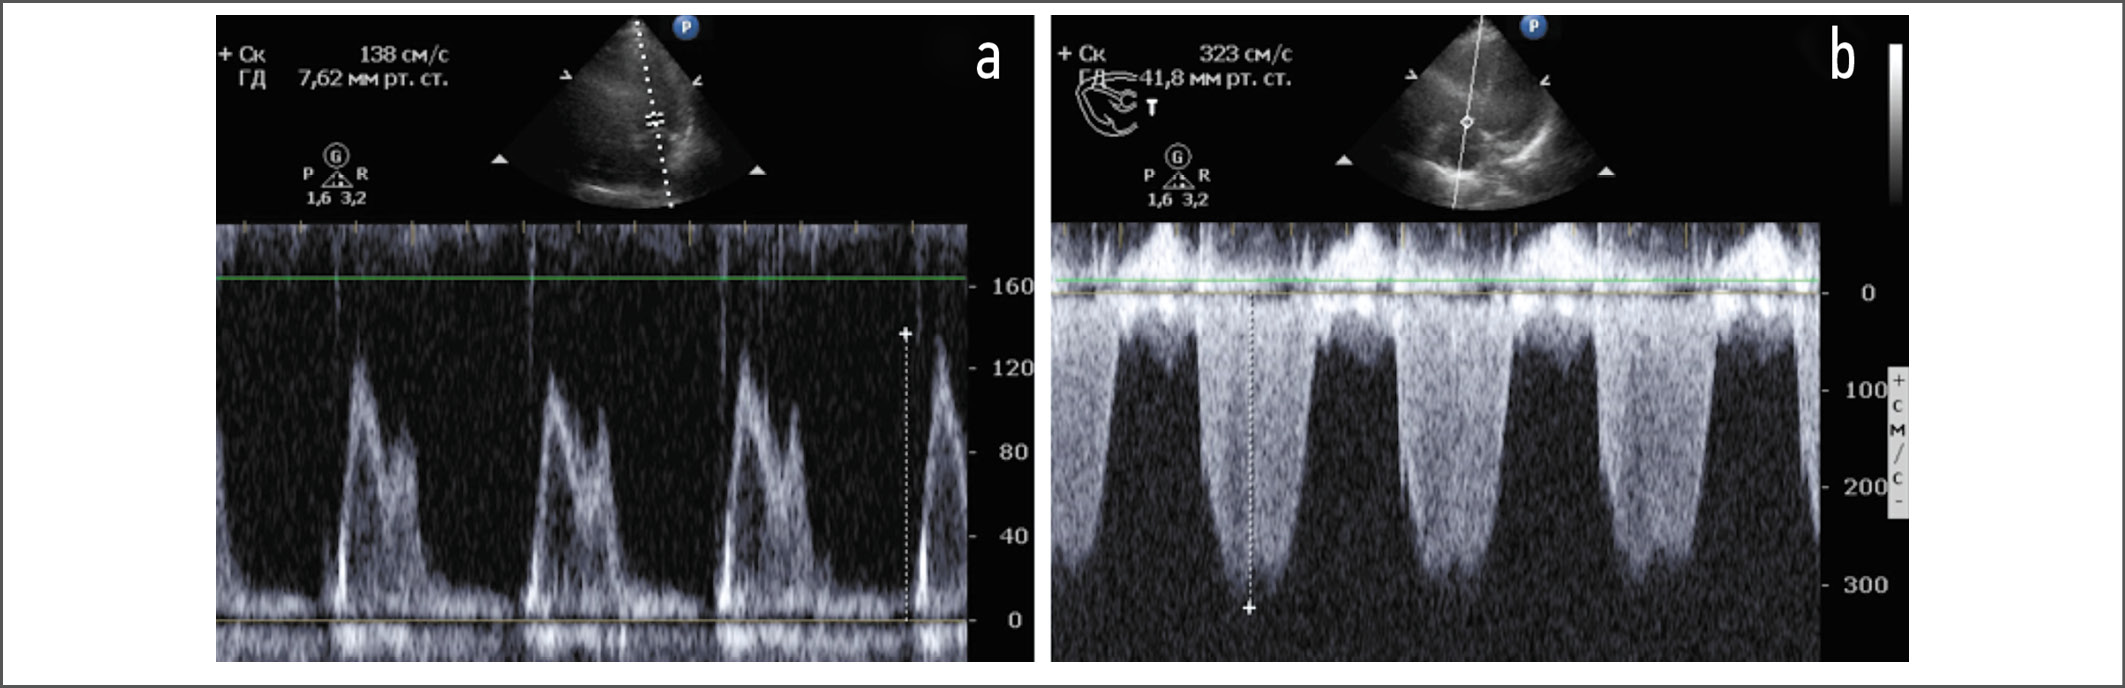

Стандартная электрокардиография: P – 0,11 с, PQ – 0,15 с, QRS – 0,13 с, Q–Tc – 0,47 с. Ритм синусовый, с частотой сердечных сокращений 73 в минуту, полная блокада правой ножки пучка Гиса. По результатам ЭхоКГ установлено, что миокард не утолщен, индекс массы миокарда ЛЖ (ИММЛЖ) составляет 76 г/м², полости сердца не расширены. Индекс объема левого предсердия (ЛП) – 22 мл/м². Фракция выброса ЛЖ по Симпсону – 71%. Ударный объем ЛЖ незначительно снижен (42 мл). Нарушений кинетики миокарда не выявлено. При допплеровской оценке трансмитрального кровотока получено расчетное отношение максимальной скорости раннего наполнения к максимальной скорости позднего наполнения в диастолу (Е/А, ед), составившее 1,4. Пиковая тканевая скорость раннего диастолического смещения (e’) септальной и латеральной частей кольца митрального клапана оказалась равной 6,7 и 8,79 см/с соответственно, усредненные значения показателей e’ и Е/e’ – 7,5 и 17,3 ед соответственно. Отмечена трикуспидальная регургитация 2-й степени, скорость которой составила 3,23 м/с. Створки митрального и аортального клапанов уплотнены. Расчетное давление в легочной артерии – 45 мм рт. ст. Листки перикарда не утолщены, выпота в полости перикарда нет. На рис. 1, 2 представлены результаты допплерографии.

Рис. 2. Допплерография трансмитрального и транстрикуспидального кровотока: a – ускорение волны Е трансмитрального кровотока до 1,38 м/с и соотношение Е/А<2; b – увеличение скорости трикуспидальной регургитации до 323 см/с.

Fig. 2. Dopplerography of the transmitral and transtricuspid blood flow: a – the acceleration of the wave E of the transmitral blood flow up to 1,38 m/s and the ratio E/A<2; b – an increase in the speed of tricuspid regurgitation up to 323 cm/s.

В ходе ЭхоКГ у нашей пациентки установлены признаки ДДЛЖ псевдонормального типа. О факте диастолической дисфункции свидетельствовали 3 из 4 критериев, принятых для пациентов с синусовым ритмом и нормальной фракцией выброса ЛЖ: Е/e’>14; e’ септальная <7 см/с и e’ латеральная <10 см/с; скорость трикуспидальной регургитации >2,8 м/с [14]. Отсутствовал единственный (4-й) критерий – дилатация ЛП. С учетом нахождения параметра трансмитрального кровотока Е/А в диапазоне >0,8 и <2,0 нами констатирован псевдонормальный тип (2-я степень) ДДЛЖ. Нормальный объем ЛП возможно рассматривать как один из признаков того, что ДДЛЖ находится в относительно компенсированной стадии.